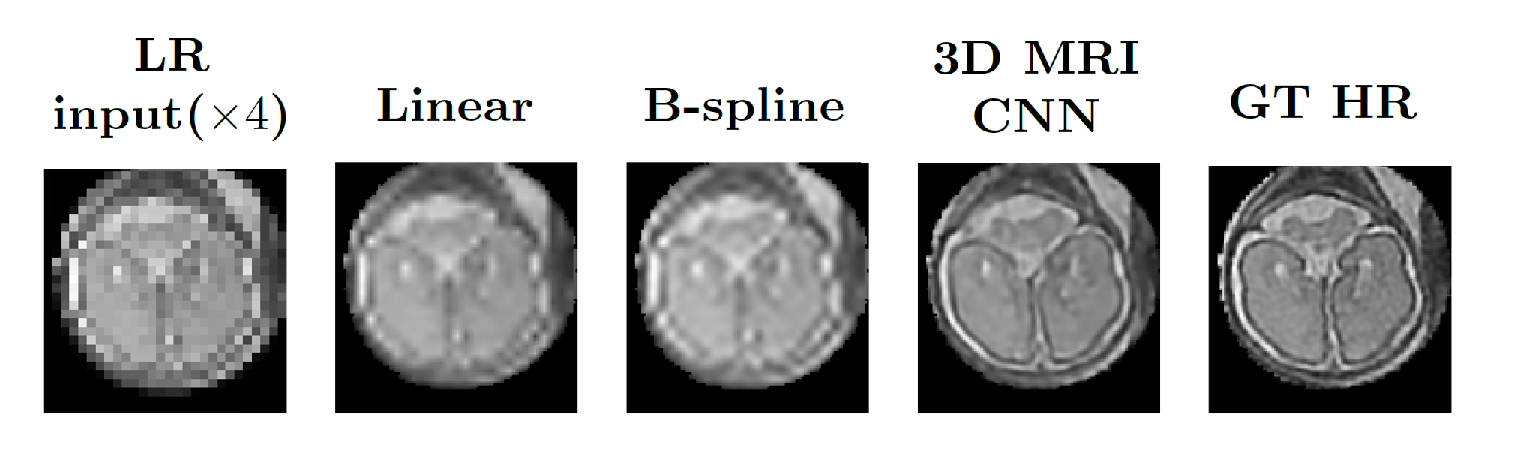

By learning problem specific HR synthesis models, our 3D MRI CNN strategy outperforms the naïve baseline up-sampling, quantitatively improving the quality of the inferred HR imagery. Fig. 2 exhibits an example of qualitative improvement in orthogonal fetal MRI test-stack axes.

| LR input() | Linear | B-spline | 3D MRI CNN | GT HR | |

|

Axial |

|

|

|

|

|

|

Sagittal |

|

|

|

|

|

|

Coronal |

|

|

|

|

|